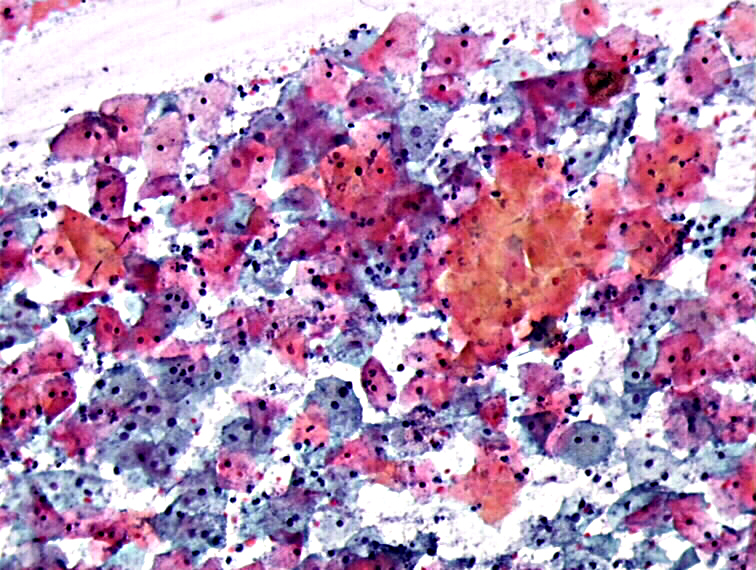

Cytopathology of the uterine cervix digital atlas Thymic Hyperplasia Covid Vaccine Thymic epithelial tumors (tet) are rare malignancies associated with dysregulation of the immune system and humoral. Measurement of thymic function may help identify children and adults with immune dysfunction who are at risk of developing severe. 1), possibly as an immunologic response to. Histology showed hyperplasia of the thymus without infiltration of the lymphoma (fig. It is known that thymus. Thymic Hyperplasia Covid Vaccine.

Cytopathology of the uterine cervix digital atlas Thymic Hyperplasia Covid Vaccine Histology showed hyperplasia of the thymus without infiltration of the lymphoma (fig. It is known that thymus morphology changes in. Measurement of thymic function may help identify children and adults with immune dysfunction who are at risk of developing severe. Thymic epithelial tumors (tet) are rare malignancies associated with dysregulation of the immune system and humoral. 1), possibly as an. Thymic Hyperplasia Covid Vaccine.